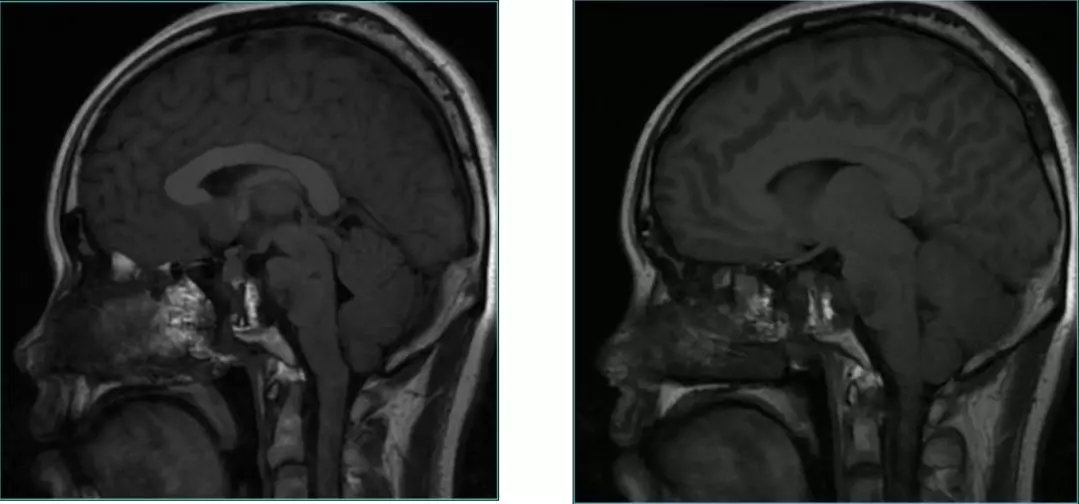

Post-op MRI with contrast

Post-op MRI

General condition is good.

No CSF fistula, double Vision improved.